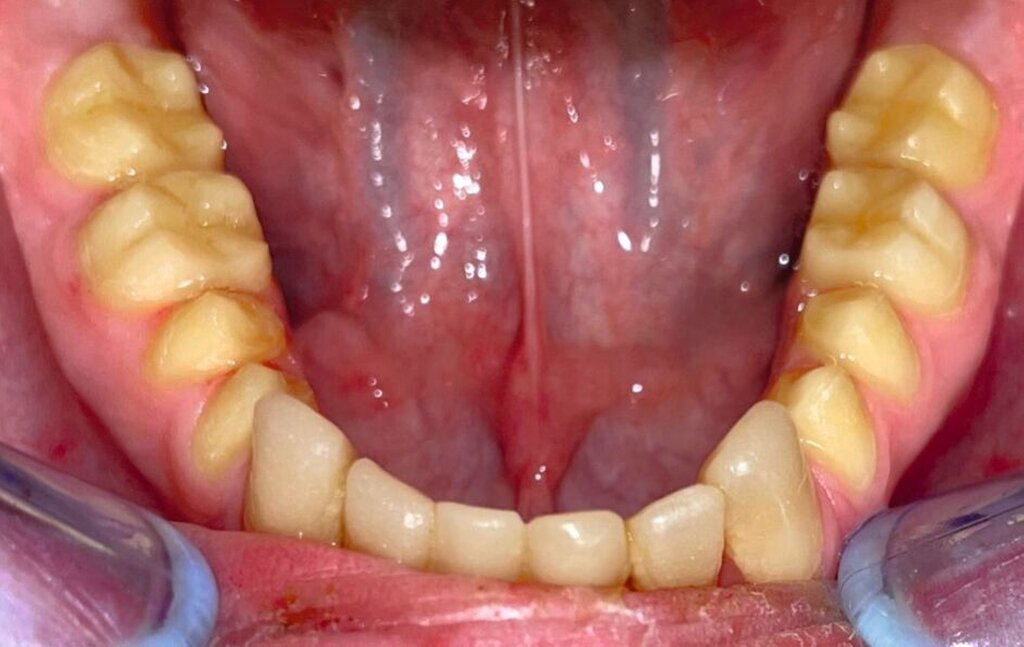

Die restaurative Versorgung erfolgte in zwei Phasen: Die Frontzähne wurden im Jahr 2018 (Abbildungen 7 und 8), die Seitenzähne im Jahr 2023 behandelt (Abbildungen 9 bis 12). Im Jahr 2018 fiel die Therapieentscheidung auf indirekte Restaurationen, da eine mangelnde Adhärenz des Patienten vorlag, die sich in geringer Geduld für längere Sitzungen äußerte. Zudem war über einen längeren Zeitraum keine zuverlässige Trockenlegung möglich. Durch diese Vorgehensweise konnten die Anzahl und die Dauer der Behandlungstermine reduziert werden.

Die Therapie begann mit einer PZR und der Anfertigung eines diagnostischen Wax-ups auf Situationsmodellen. Dieses wurde in PMMA (PalaVeneer Dentine, Kulzer) umgesetzt. Nach Reinigung der Frontzähne mit Bürstchen und fluoridfreier Polierpaste erfolgte die Anprobe der Kronen. Anschließend wurden die Kronen nach Konditionierung (Clearfil SE Bond, Kuraray Dental) mit einem Befestigungskomposit (Variolink Esthetic DC, Ivoclar Vivadent) unter relativer Trockenlegung mittels Watterollen, Speichelschnecke und Sauger definitiv eingegliedert.